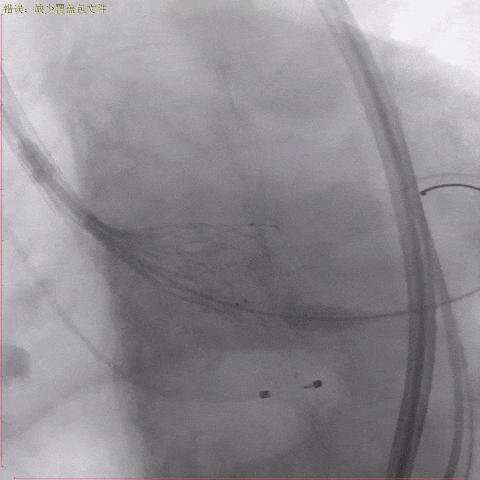

术中造影

主动脉根部造影